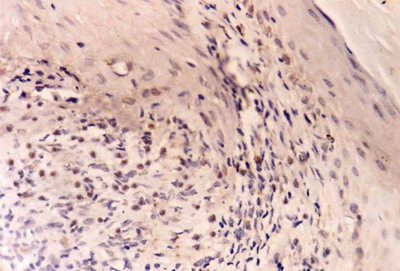

bcl-2 expression

-Control skin showed weak bcl-2 immuno-reactivity as brownish cytoplasmic staining in basal layer in 2 specimens and moderate in 3 specimens (fig 4). Dermal lymphocytes were negative for bcl-2 expression in all specimens. In LP lesions, bcl-2 was weakly expressed in the basal keratinocytes as cytoplasmic and membranous brownish staining in 4 specimens and was absent in 6 specimens. On the other hand, dermal lymphocytes showed strong bcl-2 expression in all cases (fig 5).

-After treatment: increased bcl-2 expression in basal and suprabasal layers was observed in all specimens while lymphocytes showed marked decrease in bcl-2 positivity in 6 samples and negative staining in 4 samples (fig 6).

Fig 5: A case of LP before treatment showing weak bcl-2 expression in basal keratinocytes and strong expression in dermal lymphocytes. (ABC, Meyer s HX counter stain x 400)

Fig 6: After treatment with NB-UVB, increased bcl-2 expression in basal keratinocytes and marked decrease in bcl-2 positivity in dermal lymphocytes. (ABC, Meyer s HX counter stain x 400)

The low level of bcl-2 expression in LP lesions before treatment is in agreement with other authors [4,20]. Similar results were reported in oral LP [2,16,18]. The low expression of this anti-apoptotic protein might promote apoptosis of keratinocytes in LP. Hussein et al reported [4] that the low bcl-2 expression in the face of apoptosis of basal cells suggests the concomitant loss of other pro-survival molecules or increase in the pro-apoptotic molecules in the lesions of LP. Boyd et al [20] suggested that the low expression of bcl-2 in LP might indicate that bcl-2 is not prominently involved in epidermal changes in LP and the role of other members of this oncogene family needs to be elucidated. The increased expression of bcl-2 after NB-UVB treatment may be attributed to restoration of normal basal activity in the healing lesions. It is well known that in normal skin the actively proliferating cells of basal keratinocytes typically express bcl-2 which protects them against apoptotic stimuli [24].

On the other hand, the strong expression of bcl-2 in dermal lymphocytes in lesions of LP before treatment inhibits the apoptosis in lymphocytes that strengthens cell-mediated immune process causing chronicity of the disease [22]. After treatment with NB-UVB, the marked decrease in bcl-2 expression leads lymphocytes to undergo apoptosis which might contribute to healing of the lesions [25].